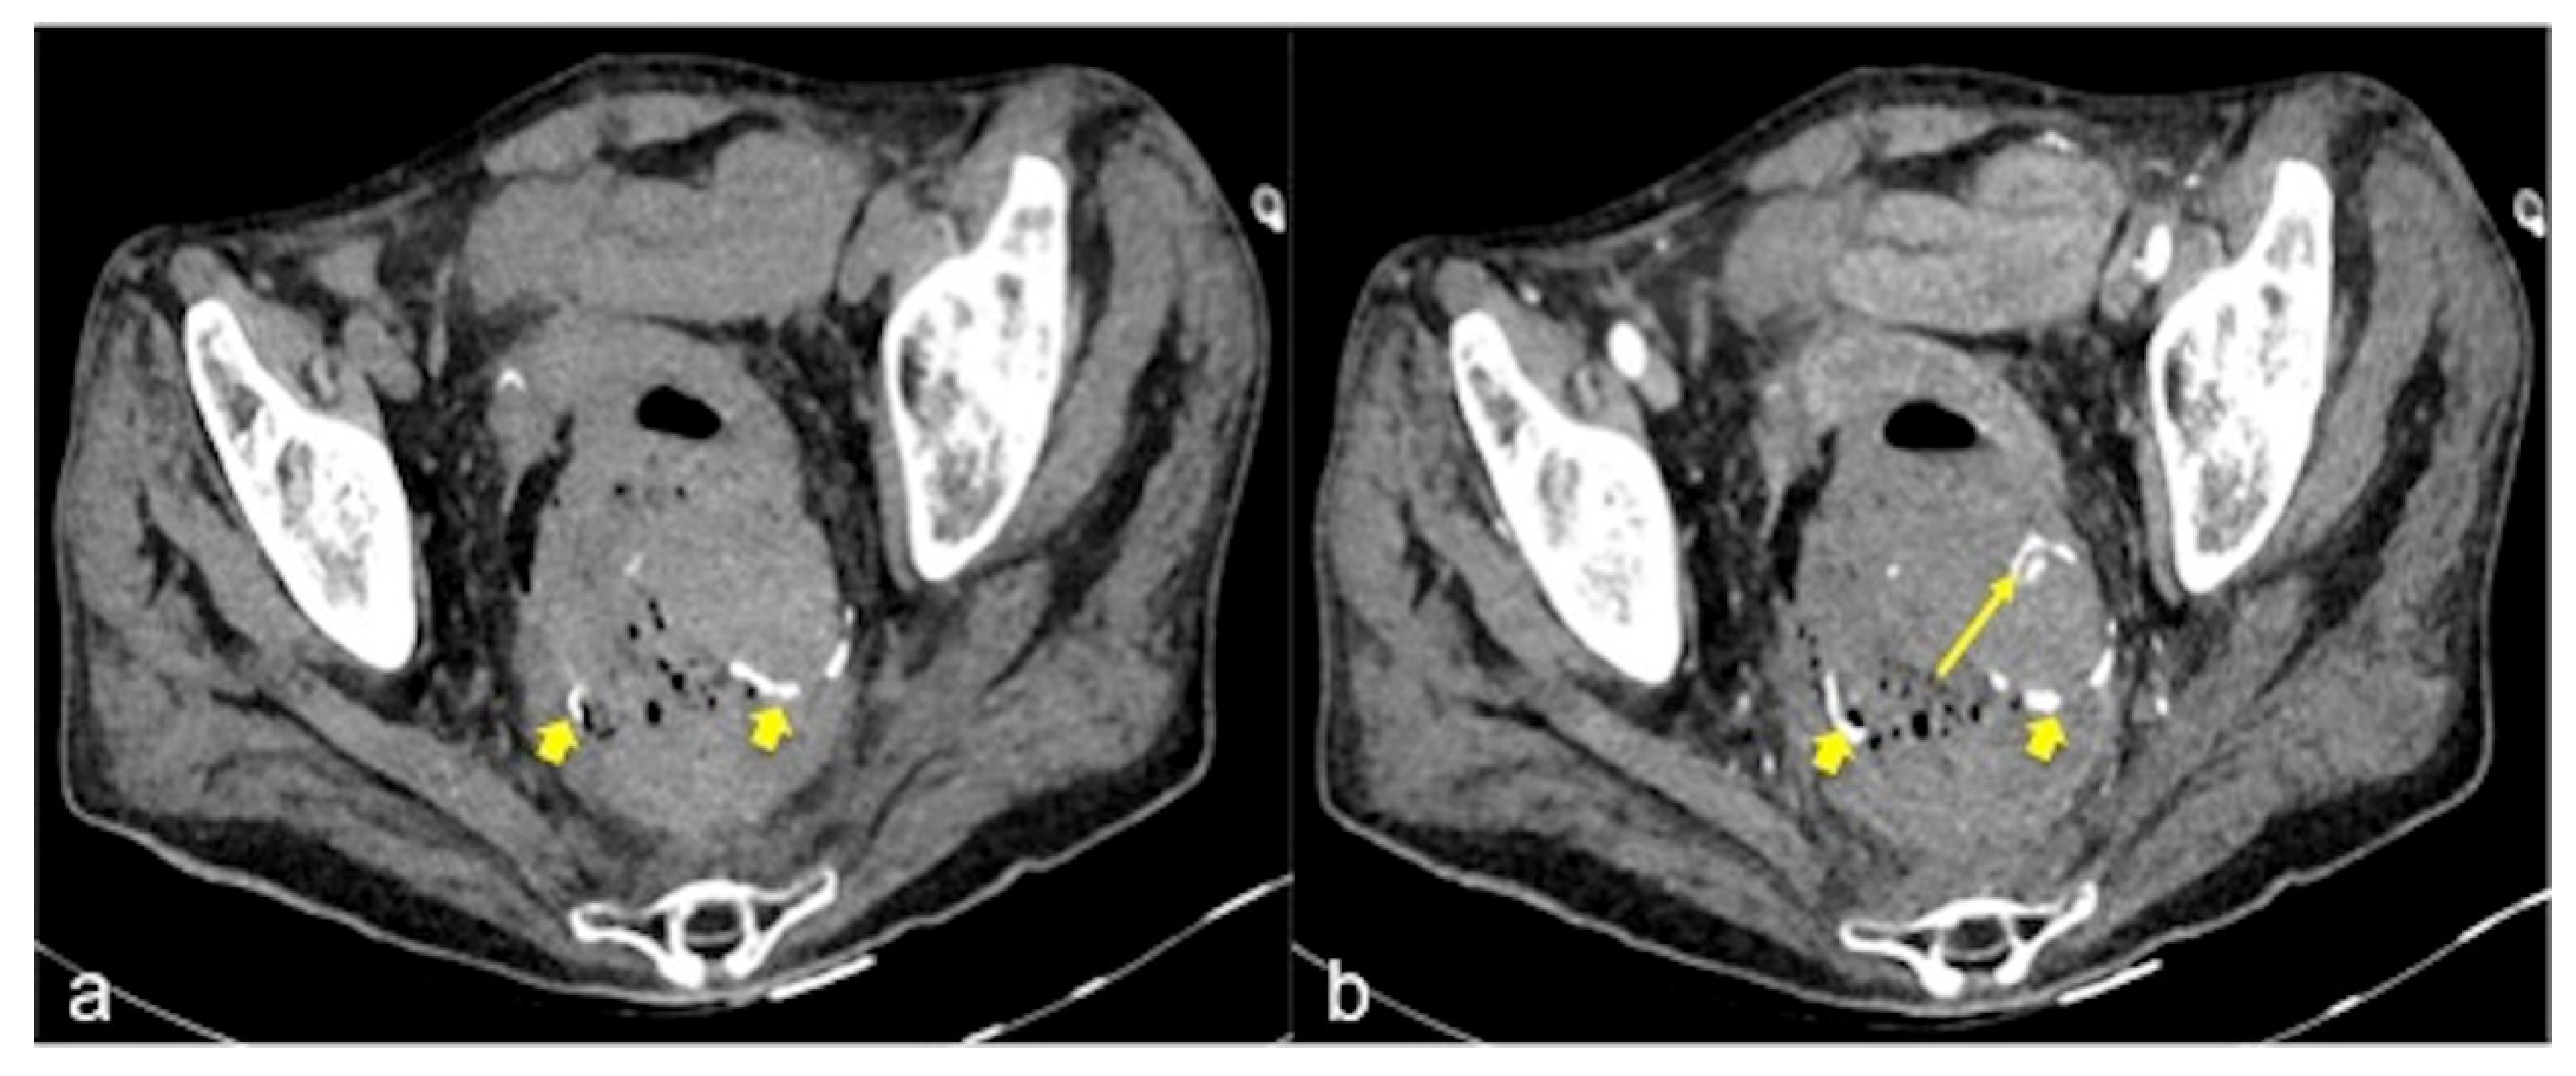

| Diverticulosis (Figure 33) | Asymptomatic or bleeding. | Protruding sacs where the vessels pass through the muscularis layer, between the mesenteric and antimesenteric taenia. |

| Angiodysplasia (Figure 5 and Figure 34) | Asymptomatic or bleeding. | Small hyperdense nodules within the intestinal wall, best defined in the portal phase of the study. |